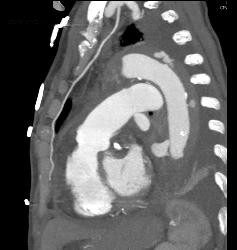

Leak From Descending Aorta